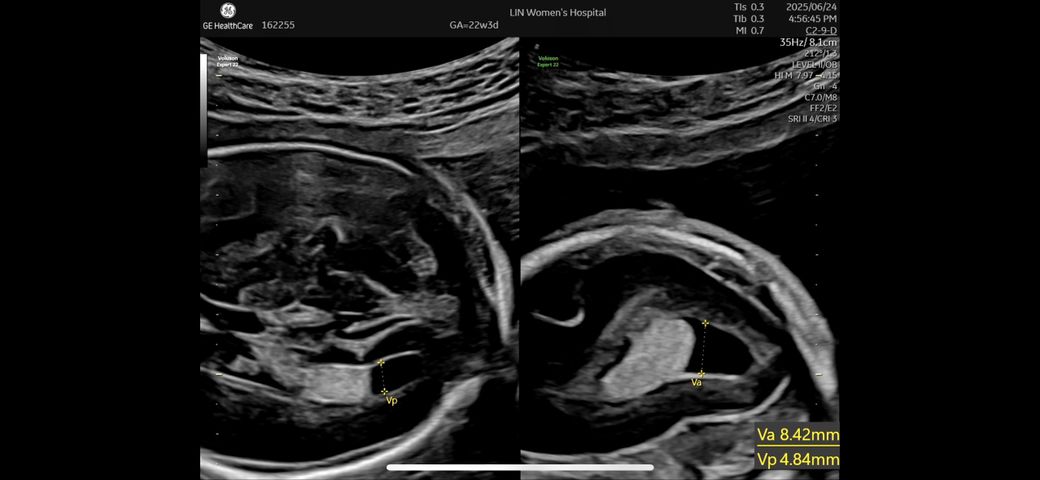

뇌실크기가 10mm 이상 나올 경우 경계해야한다고 들었습니다. 제 아기는 va 8.42mm vp 4.84mm 인데요. Va가 더 크지만 Vp가 10mm 안에 들어오기만 하면 정상인게 맞을지요?

• 1번 째 사진